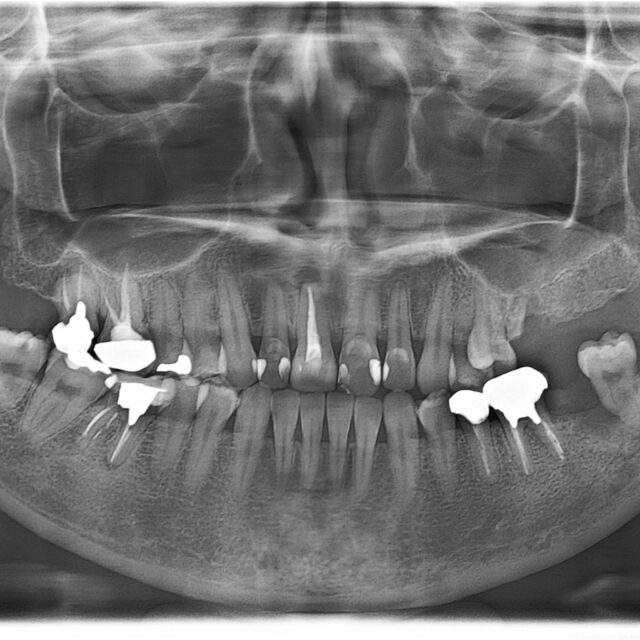

症例case05 Marfan症候群を伴う叢生症例 (14歳/女性 /6ヶ月)